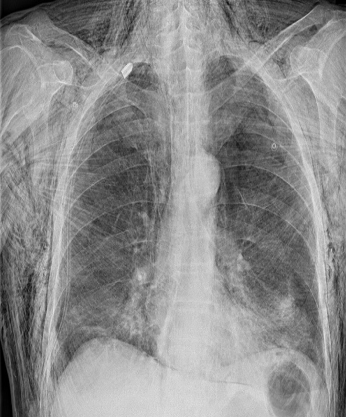

Traumatic/Surgical pneumomediastinum w/ subcutaneous emphysema

X-ray chest (PA view): Extensive subcutaneous emphysema is seen as linear lucencies throughout the soft tissues of the thorax, neck, and upper abdomen. pneumomediastinum is seen along the trachea, main bronchi, and cardiac silhouette .A chest tube is in place, with its tip in the apex of the right hemithorax.